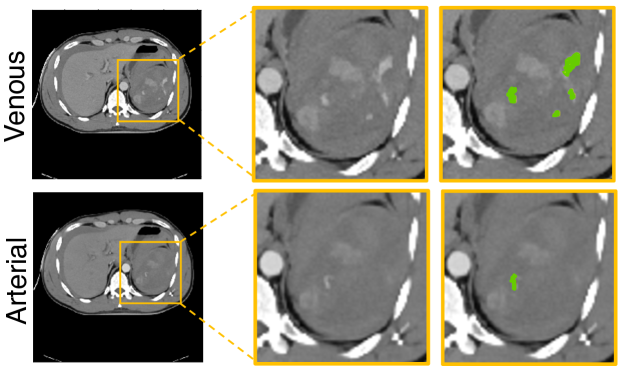

Refer to caption

Figure 1: Visual comparison of arterial and venous images (after alignment) as well as the manual segmentation of the splenic vascular injury. The injury volumes are different across phases.